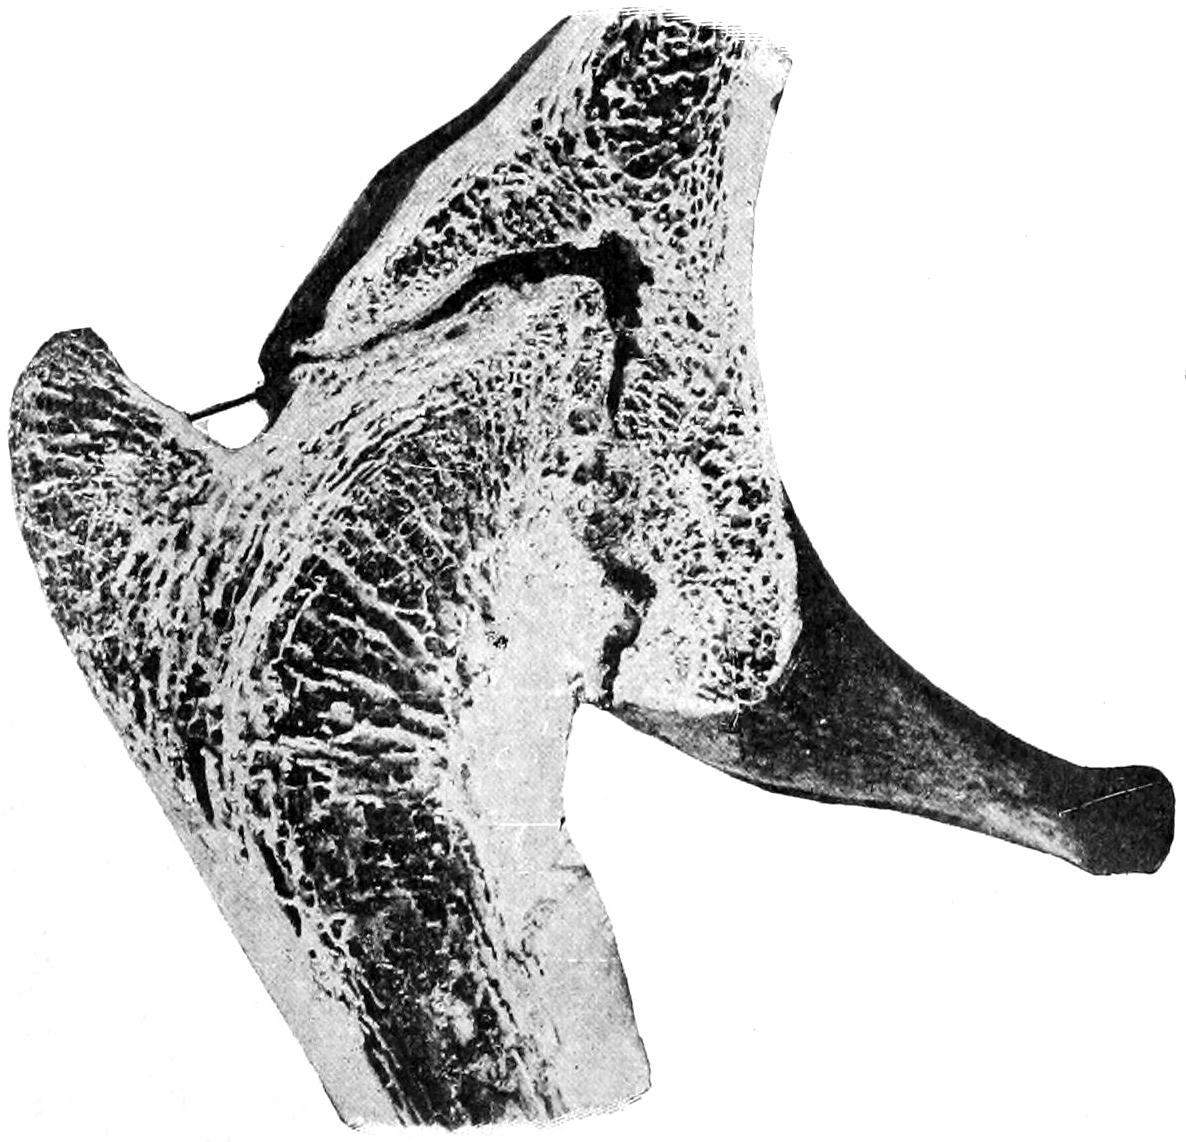

Fig. 1

Congenital hypertrophy: gigantism of both lower extremities. (Case of Dr. Graefe [Sandusky].)